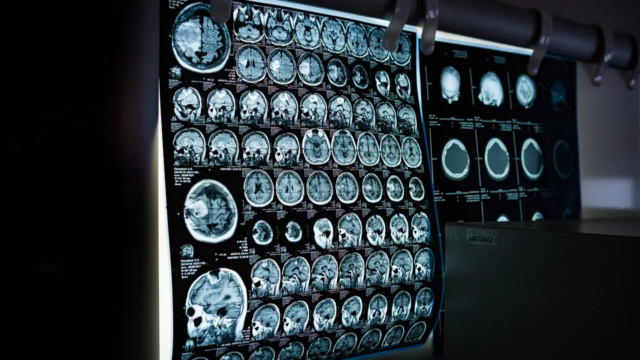

Tradicionalmente visto como una enfermedad de las personas mayores, el accidente cerebrovascular afecta ahora a un número creciente de adultos jóvenes menores de 40 años en edad laboral. Los expertos atribuyen la causa a malas elecciones de estilo de vida, estrés y falta de conciencia sobre las primeras señales de alerta.

Un derrame cerebral ocurre cuando se interrumpe el suministro de sangre al cerebro, lo que provoca daño a las células cerebrales. Las señales de advertencia clave se pueden recordar a través de SER RÁPIDO: pérdida del equilibrio, problemas de visión, cara caída, debilidad en los brazos, dificultad para hablar y tiempo para actuar rápidamente.

El tratamiento del accidente cerebrovascular a menudo incluye medicamentos anticoagulantes, procedimientos de trombectomía y terapias de rehabilitación destinadas a restaurar la función neurológica y la calidad de vida.